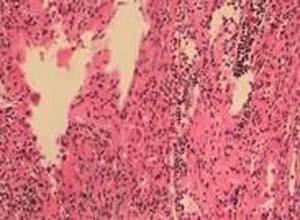

简介先天自愈性朗格汉斯组织细胞增生症(Congenital Self-Healing langerhans Histiocytosis,CSLH)又名先天性自愈性网状组织细胞增生症本病于1973年由Hashimoto和Pritzker报告,故又名Hashimoto-Pritzker病,呈自限性、良性经过,仅有皮损而无系统性损害;其皮肤损害特点和组织病理象,实际上与朗格汉斯细胞组织细胞增生症相似,免疫组化检查S-100蛋白,CDIa(OKT6)亦阳性,且超微检查也可见到Birbeck颗粒;因而有人将本病列入朗格汉斯组织细胞增生症病谱中的最良性型。